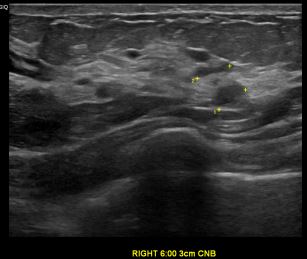

상기환자는 외부검진이상소견  정밀검사위해 내원하신 40대 중반

여성분으로 의심스러운 우측유방혹 조직검사 시행해 제자리암으로 진단되었습니다